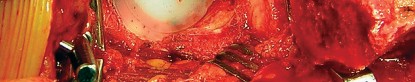

في جراحة استبدال مفصل الورك الكلي، يتم استبدال رأس عظم الفخذ التالف بمكون معدني كروي، ويتم استبدال الحُق الطبيعي المتضرر بمكون حُقي صناعي. المكون الحُقي الأسمنتي هو عبارة عن كوب معدني أو بلاستيكي عالي الجودة (عادة من البولي إيثيلين) يتم تثبيته داخل تجويف الحُق في عظم الحوض باستخدام "الأسمنت العظمي" (Bone Cement)، وهو مادة بوليمرية حيوية تعمل كغراء قوي لتثبيت المكون بشكل فوري ومستقر.

جراحة استبدال مفصل الورك الكلي (Total Hip Replacement - THR)

تتضمن هذه الجراحة استبدال الأجزاء التالفة من مفصل الورك بمكونات صناعية مصنوعة من المعدن، البلاستيك عالي الجودة (البولي إيثيلين)، أو السيراميك. الهدف هو تخفيف الألم واستعادة وظيفة المفصل.